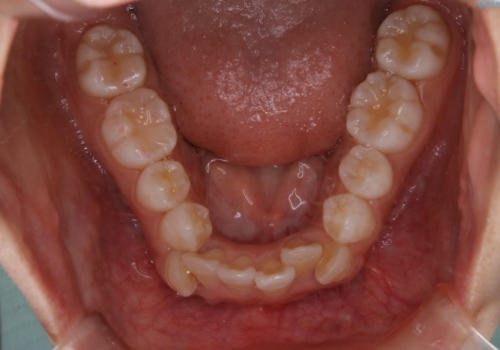

インビザライン単独での抜歯矯正治療

- 当院にてインビザライン治療を行っていた同僚の方からのご紹介でいらした方です。楽器を演奏されるとの事で、インビザラインによる矯正治療をご希望されました。治療の途中で一時的にワイヤー矯正に切り替える可能性もあることもご了承頂いた上で治療を行いました。

1日20時間以上、正しくインビザラインを使用して頂いたおかげで、ワイヤーに切り替えることなく矯正治療を終了することが出来ました。抜歯症例でしたが比較的短期間で見た目が劇的に改善し、大変喜んでいただけました。